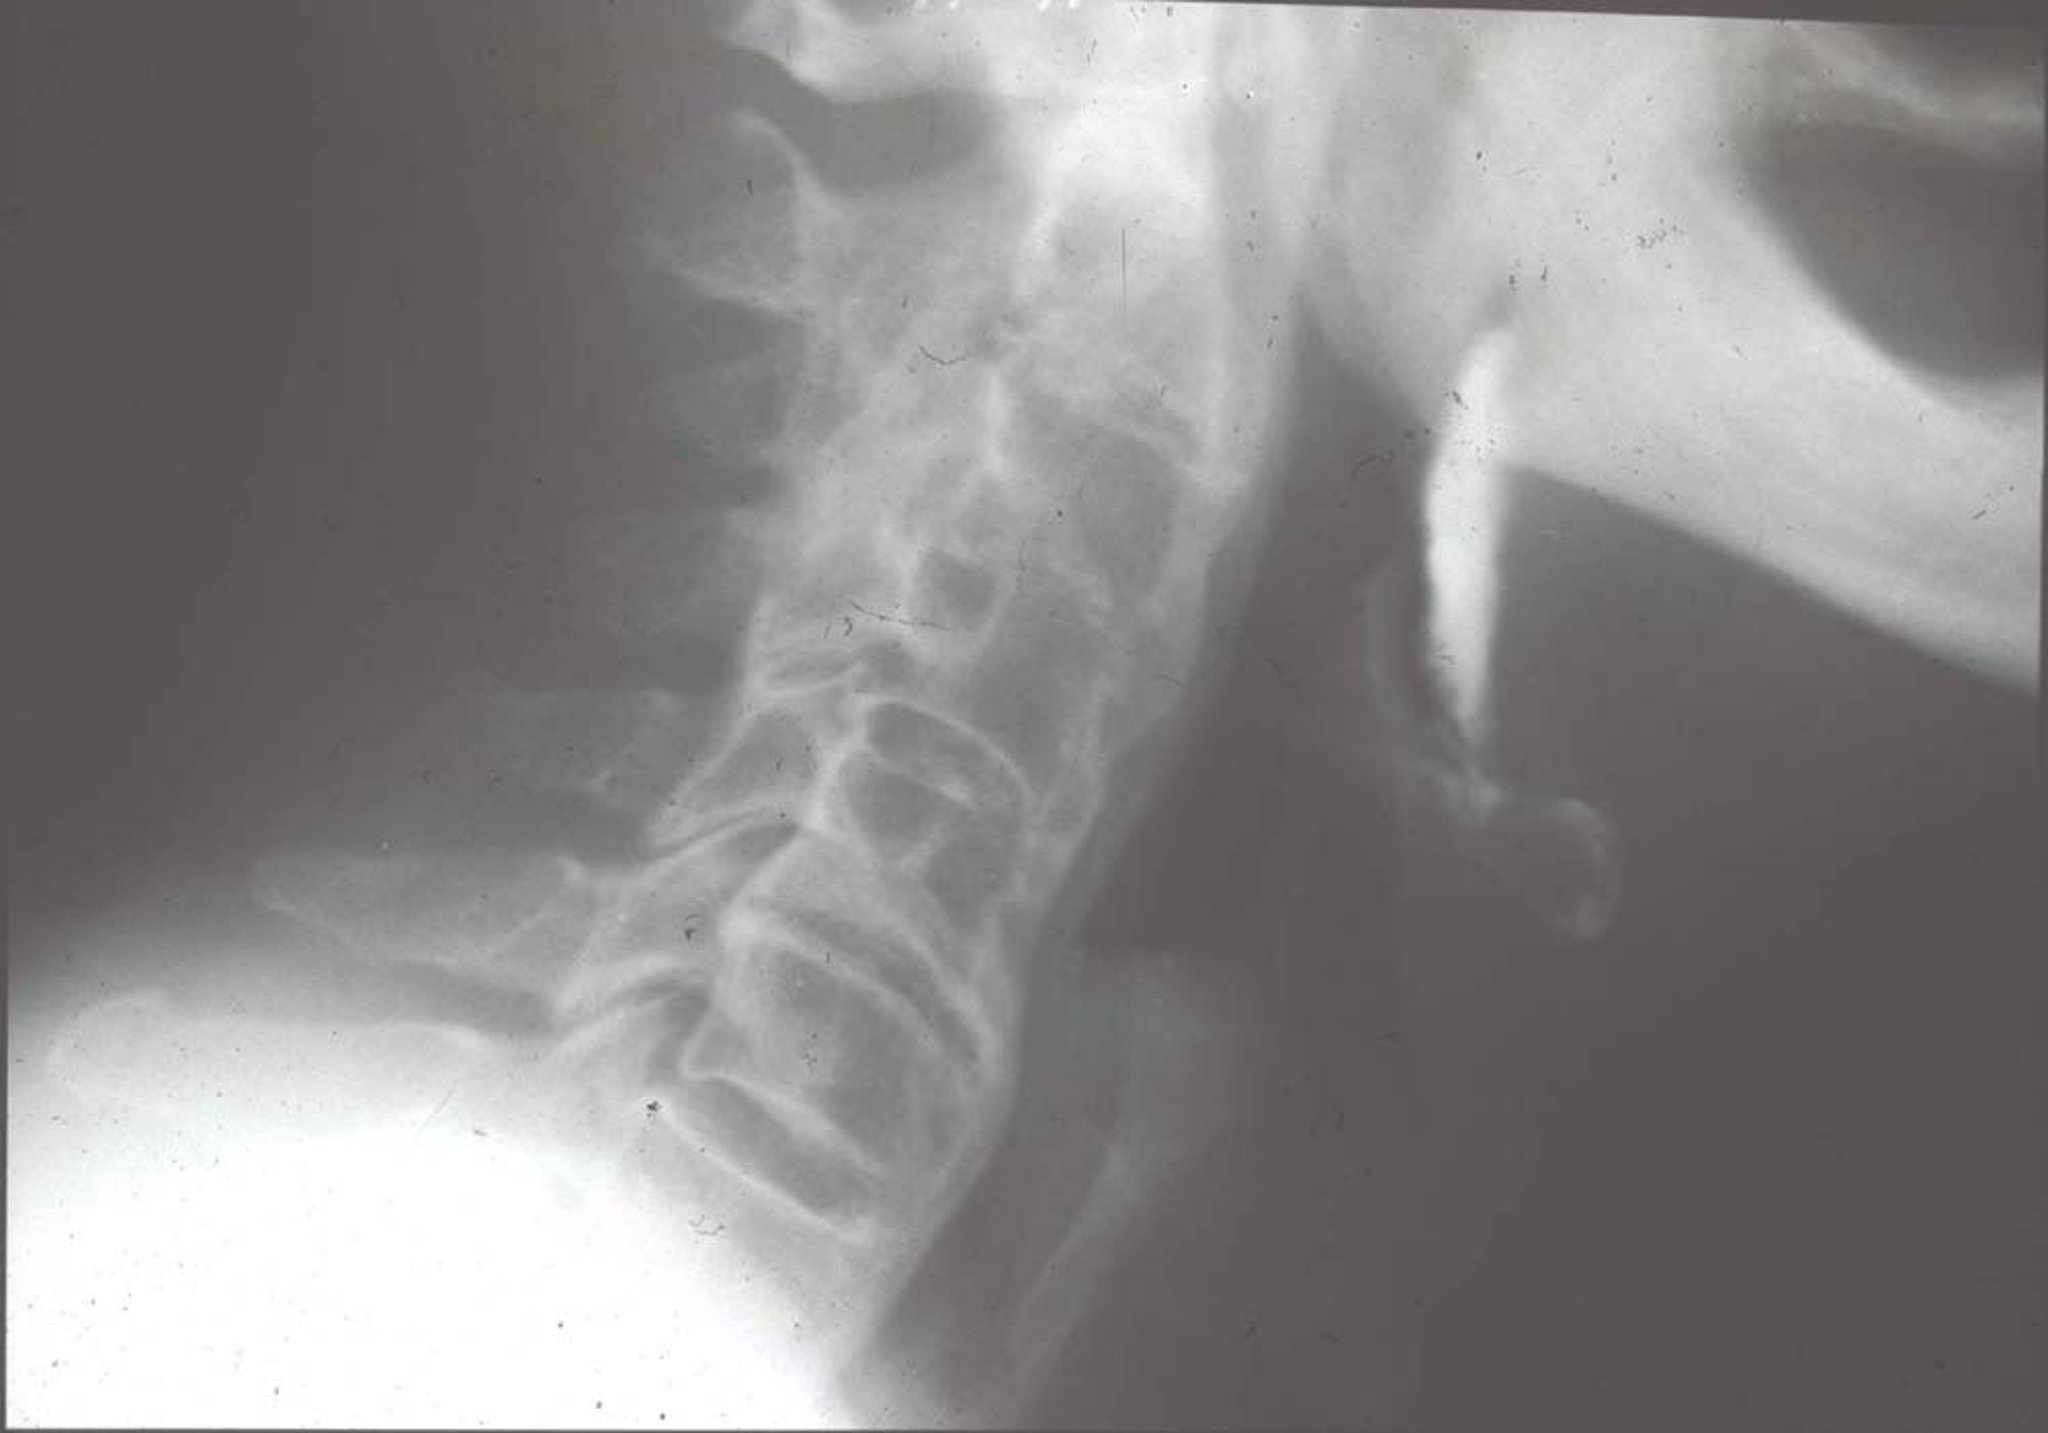

Hyperostose squelettique idiopathique diffuse (radiographie)

Les modifications caractéristiques de la radiographies comprennent de grandes ossifications antérieures par rapport aux corps vertébraux (la calcification apparaît comme si quelqu'un versait de la cire de bougie devant et sur les côtés des vertèbres), pontant plusieurs vertèbres.

Image fournie par Roy Altman, MD.